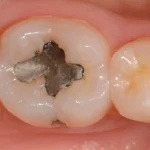

Antigamente, restaurações com amálgama de prata eram muito utilizadas nos tratamentos para cárie. Entretanto, uma de suas desvantagens é o aspecto pouco estético que elas resultam, diferentemente das resinas dentárias que possuem cores próximas aos dentes e proporcionam beleza e naturalidade às restaurações.

Confira este caso clínico de restauração dentária posterior, terceiro molar, com a resina tipo Bulk da 3M.

Passo a passo de como remover restauração de amálgama